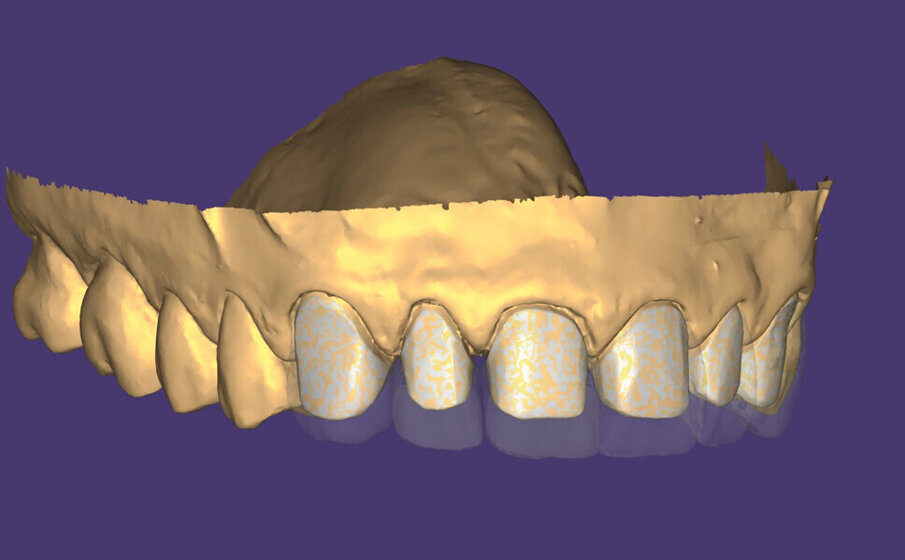

Následně byl zhotoven digitální wax-up ve frontálním úseku horní čelisti, aby bylo možno ověřit estetiku plánované rekonstrukce a vést minimálně invazivní preparaci zubů na základě zhotoveného mock-upu (obr. 8). Finální preparace (obr. 9) se z větší části omezila na interproximální oblasti (obr. 10). Poté byl proveden finální digitální otisk při aplikaci retrakční niti. (obr. 11).

V rámci digitálního designu navržené rekonstrukce byla provedena částečná redukce dolní poloviny bukální plochy plánovaných korunkových náhrad, aby bylo umožněno vrstvení keramiky pro dosažení co nejlepšího estetického výsledku (obr. 12 a 13).

Obr. 13: Konečná rekonstrukce (s prostorem pro frontální stratifikaci).